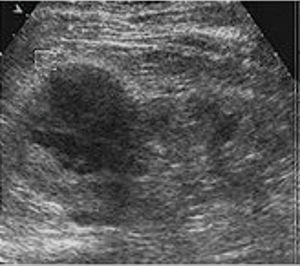

RESULTSEnrollmentFrom 15 January 2017 to 31 December 2018, patients enrolled at the Second People's Hospital of Lanzhou, Lanzhou, China and the First People's Hospital of Tian Shui GanSu Province, Tianshui, China underwent imaging examinations as a part of routine clinical care to evaluate kidney structure and size. Grayscale ultrasound (Figure 3) and CT (Figure 4) images suggested kidney lesions in 241 patients with elevated serum creatinine levels during routine clinical care. Of these patients, seven were excluded due to very high blood pressure, two were excluded because of congenital heart disorders, two women were breastfeeding and could not undergo CEUS/CECT, and 39 patients declined to undergo radiological examinations. The grayscale ultrasound, CT, CECU, CECT, and histopathology data of 191 patients were included in the analysis. A flow diagram of the study is presented in Figure 5.

CEUS showed tumor blood flow in all of the patients. CEUS detected 151 patients with malignant tumors and 40 patients with benign tumors. A total of 104 individuals had clear cell carcinoma, 35 had papillary RCC (papillary RCC-type I and papillary RCC-type II), six individuals had collecting duct carcinoma, six patients had infiltrative urothelial carcinoma, 27 individuals had angiomyolipoma, and 13 patients were diagnosed with oncocytomas, according to CEUS (Figure 6).

Contrast-enhanced ultrasound images of the kidney. A: Clear cell renal carcinoma. B: Papillary renal cell carcinoma-type I. C: Papillary renal cell carcinoma-type II. D: Infiltrative urothelial renal cell carcinoma. E: Collecting duct renal cell carcinoma. F: Angiomyolipoma. G: Oncocytoma.